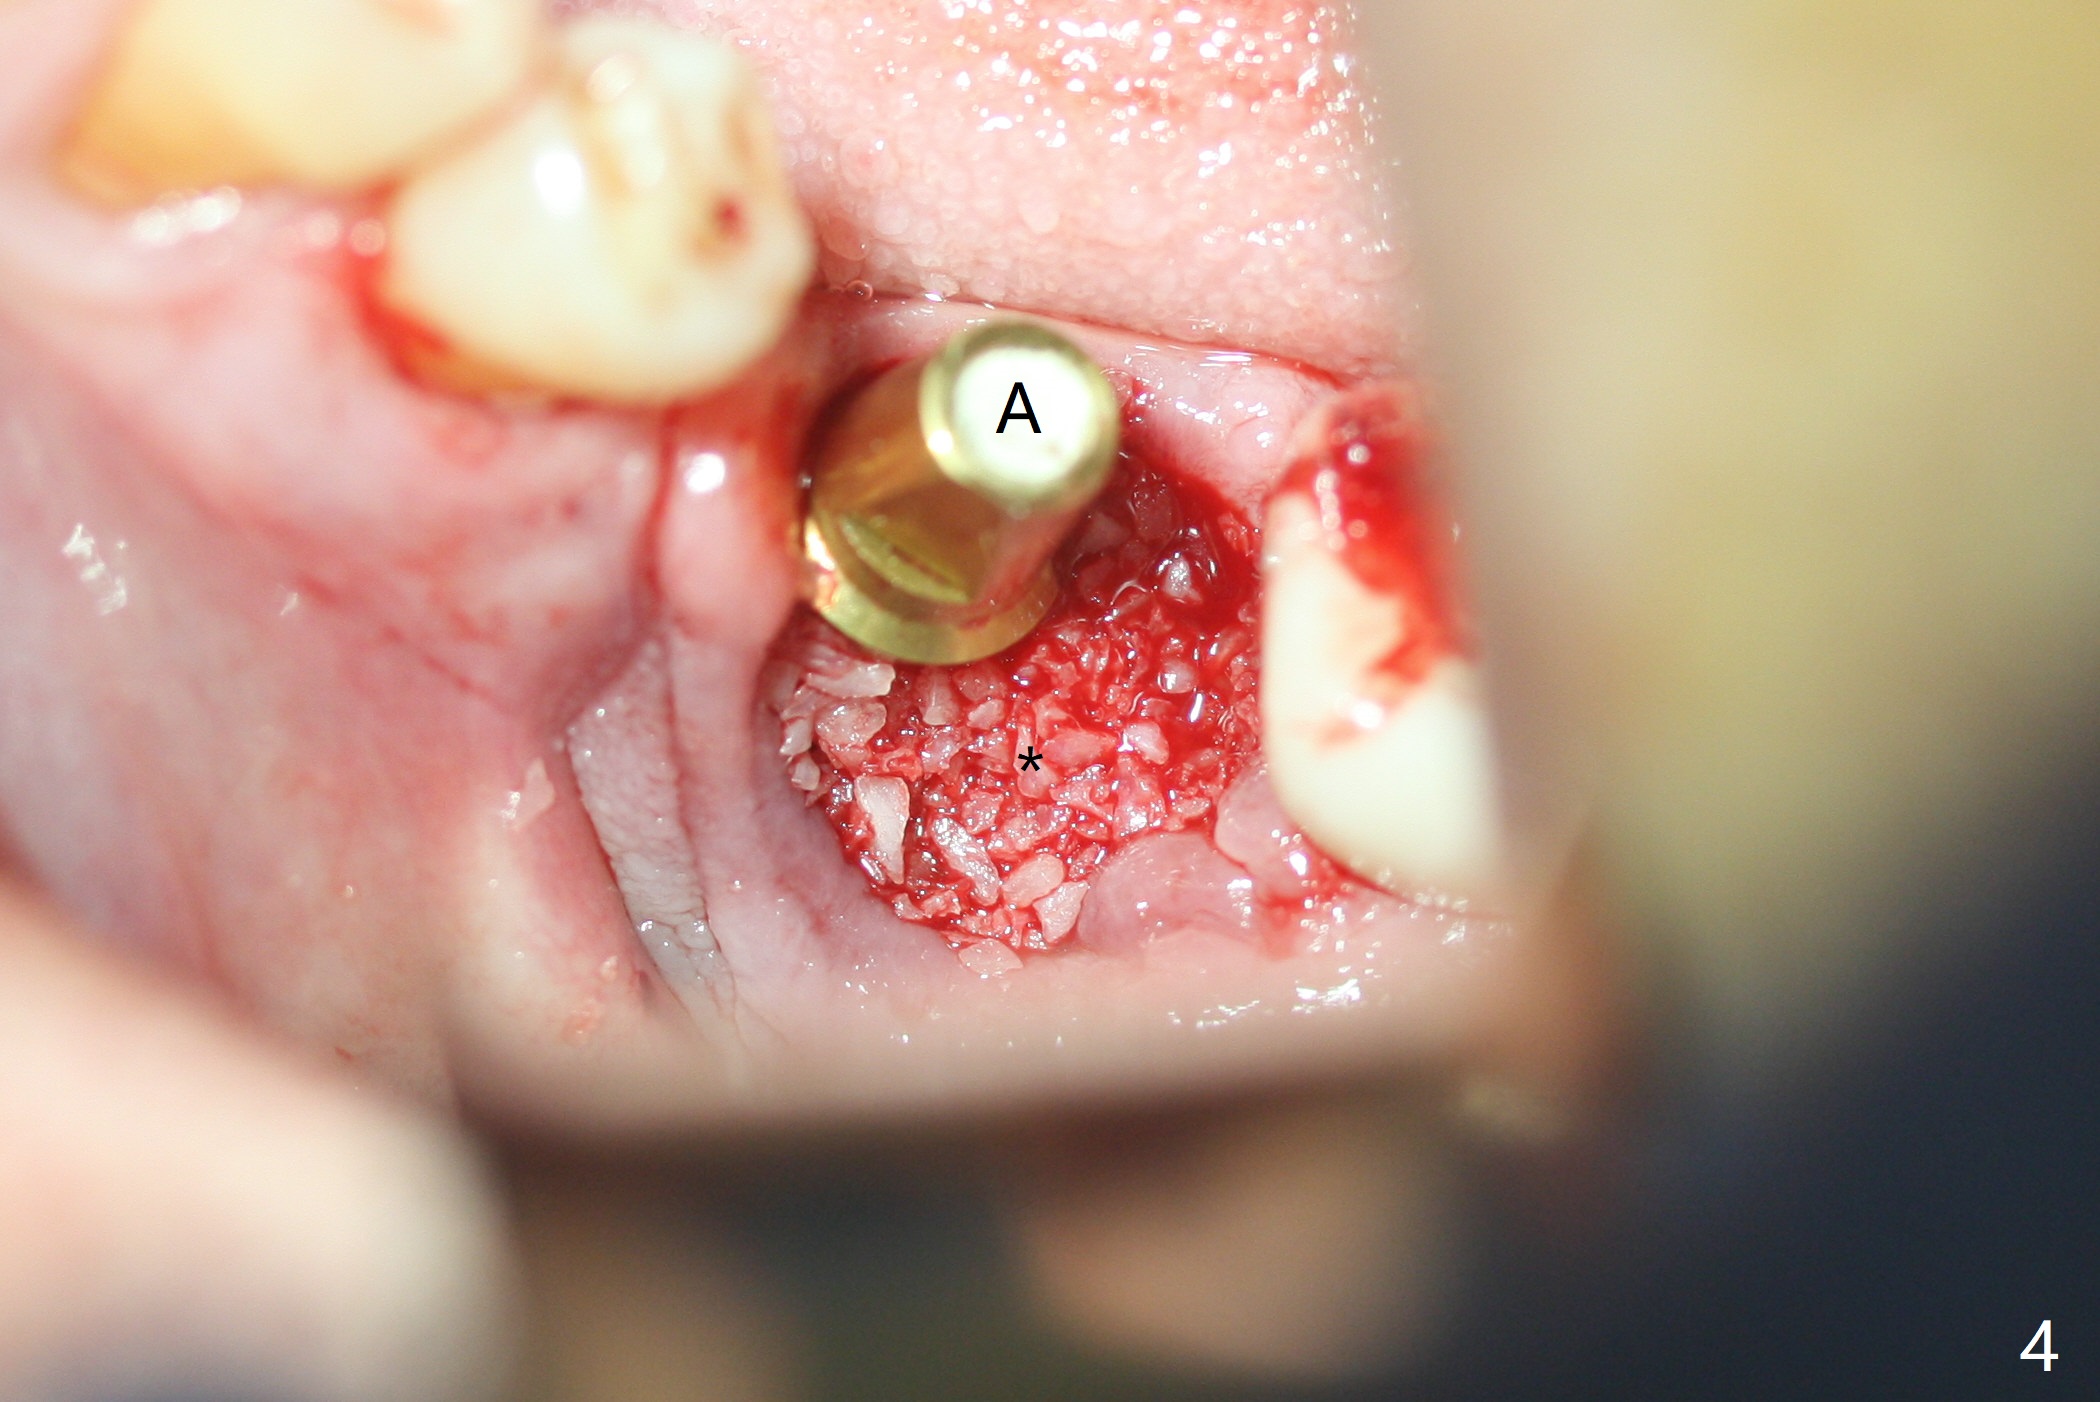

Probably due to severe infection at #19, pain control is difficult. Osteotomy has to be stopped 1.5 mm short of the design. PA taken with a 4.5x10 mm dummy implant does not show the Inferior Alveolar Canal (Fig.1), whereas CT does (Fig.2). With 6 mm clearance, block anesthesia is administered. A 5x10 mm definitive implant is placed with ease (Fig.3). The buccal bony defect is repaired by allograft (Fig.3,4 *), while the soft one by 3 pieces of PRF membrane (Fig.5). The latter is fixed in place by applying setting acrylic as an immediate provisional (Fig.6 P) over the wound, around the abutment (A) and locking into the undercut of the neighboring tooth/implant crown. The patient feels great postop. The gingiva is healthy around the provisional 8 days postop (Fig.7). The patient remains asymptomatic with the healthier gingiva surrounding the simplified provisional 22 days postop, as compared to 8 days postop (Fig.8). The socket heals when the simplified provisional is removed 1.5 months postop (Fig.9-12). The bone graft (Fig.11 ^) seems to have become a part of the regenerated gingiva. The abutment has been dislodged for 2 week (Fig.14 (3 months postop). The bone graft, albeit decreased, is 2 mm subgingival (red dashed line). There is bone distal to the implant 11 months postop (Fig.15 *). There is no bone loss 2 years postop; the UF abutment is completely seated (Fig.16).